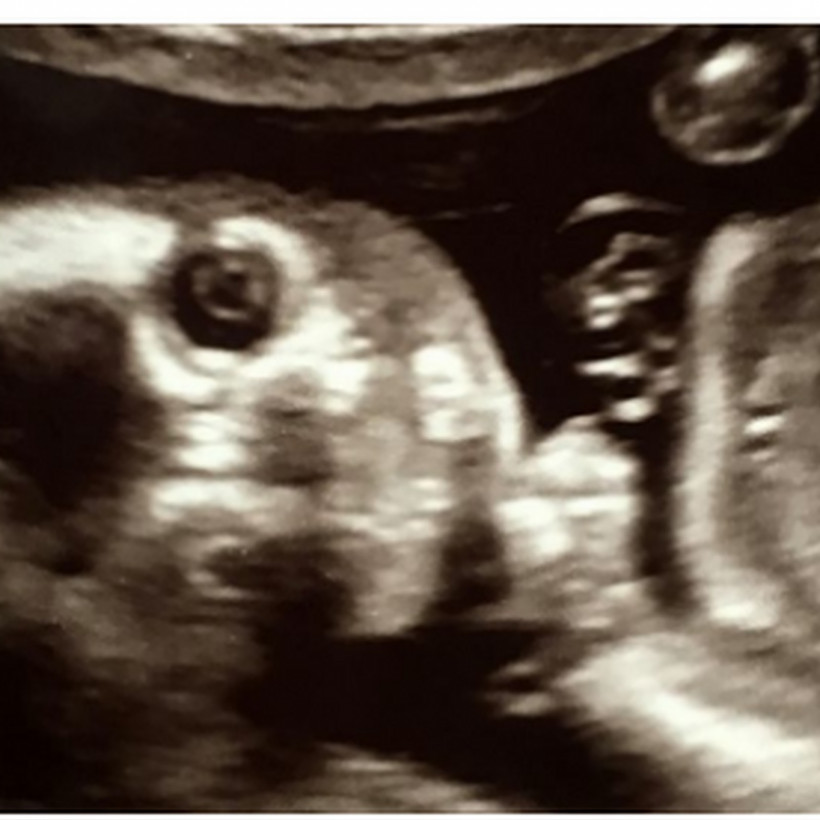

Το μεγαλύτερο σοκ της ζωής της έπαθε μια μέλλουσα μητέρα όταν υπεβλήθη στον υπέρηχο των 20 εβδομάδων προκειμένου να δει αν όλα πάνε καλά με την εγκυμοσύνη της.

Η Jo Greer, από τη Μεγάλη Βρετανία που διανύει – σύμφωνα με όσα μεταδίδει η βρετανική Mirror – την 24η εβδομάδα της εγκυμοσύνης της πήγε στον γυναικολόγο, ξάπλωσε στο ειδικό κρεβάτι και ο γιατρός της άνοιξε την οθόνη προκειμένου η μέλλουσα μαμά να δει για πρώτη φορά το προσωπάκι του μωρού που κυοφορεί. Τότε ήταν που πάγωσαν όλοι.

Δείτε στην gallery τι αντίκρισαν: